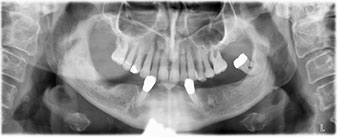

Die 64-jährige Patientin wurde mit einer Unterkiefer-Restbezahnung 38, 33 und 43 und einer klammerbefestigten Interimsprothese im Unterkiefer vorstellig (Abb. 1 und 2).

Unterkiefer-Restbezahnung

Abb. 1